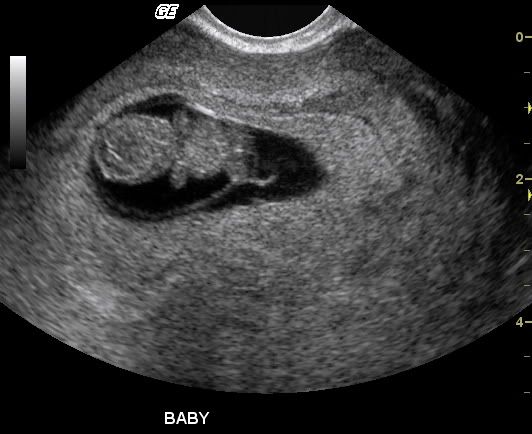

Nevertheless

Here are a couple of pics of my grandson. I don't get to hold him until July, but this early peek is nice!

This one is Mommy on the left and Grampa on the right.